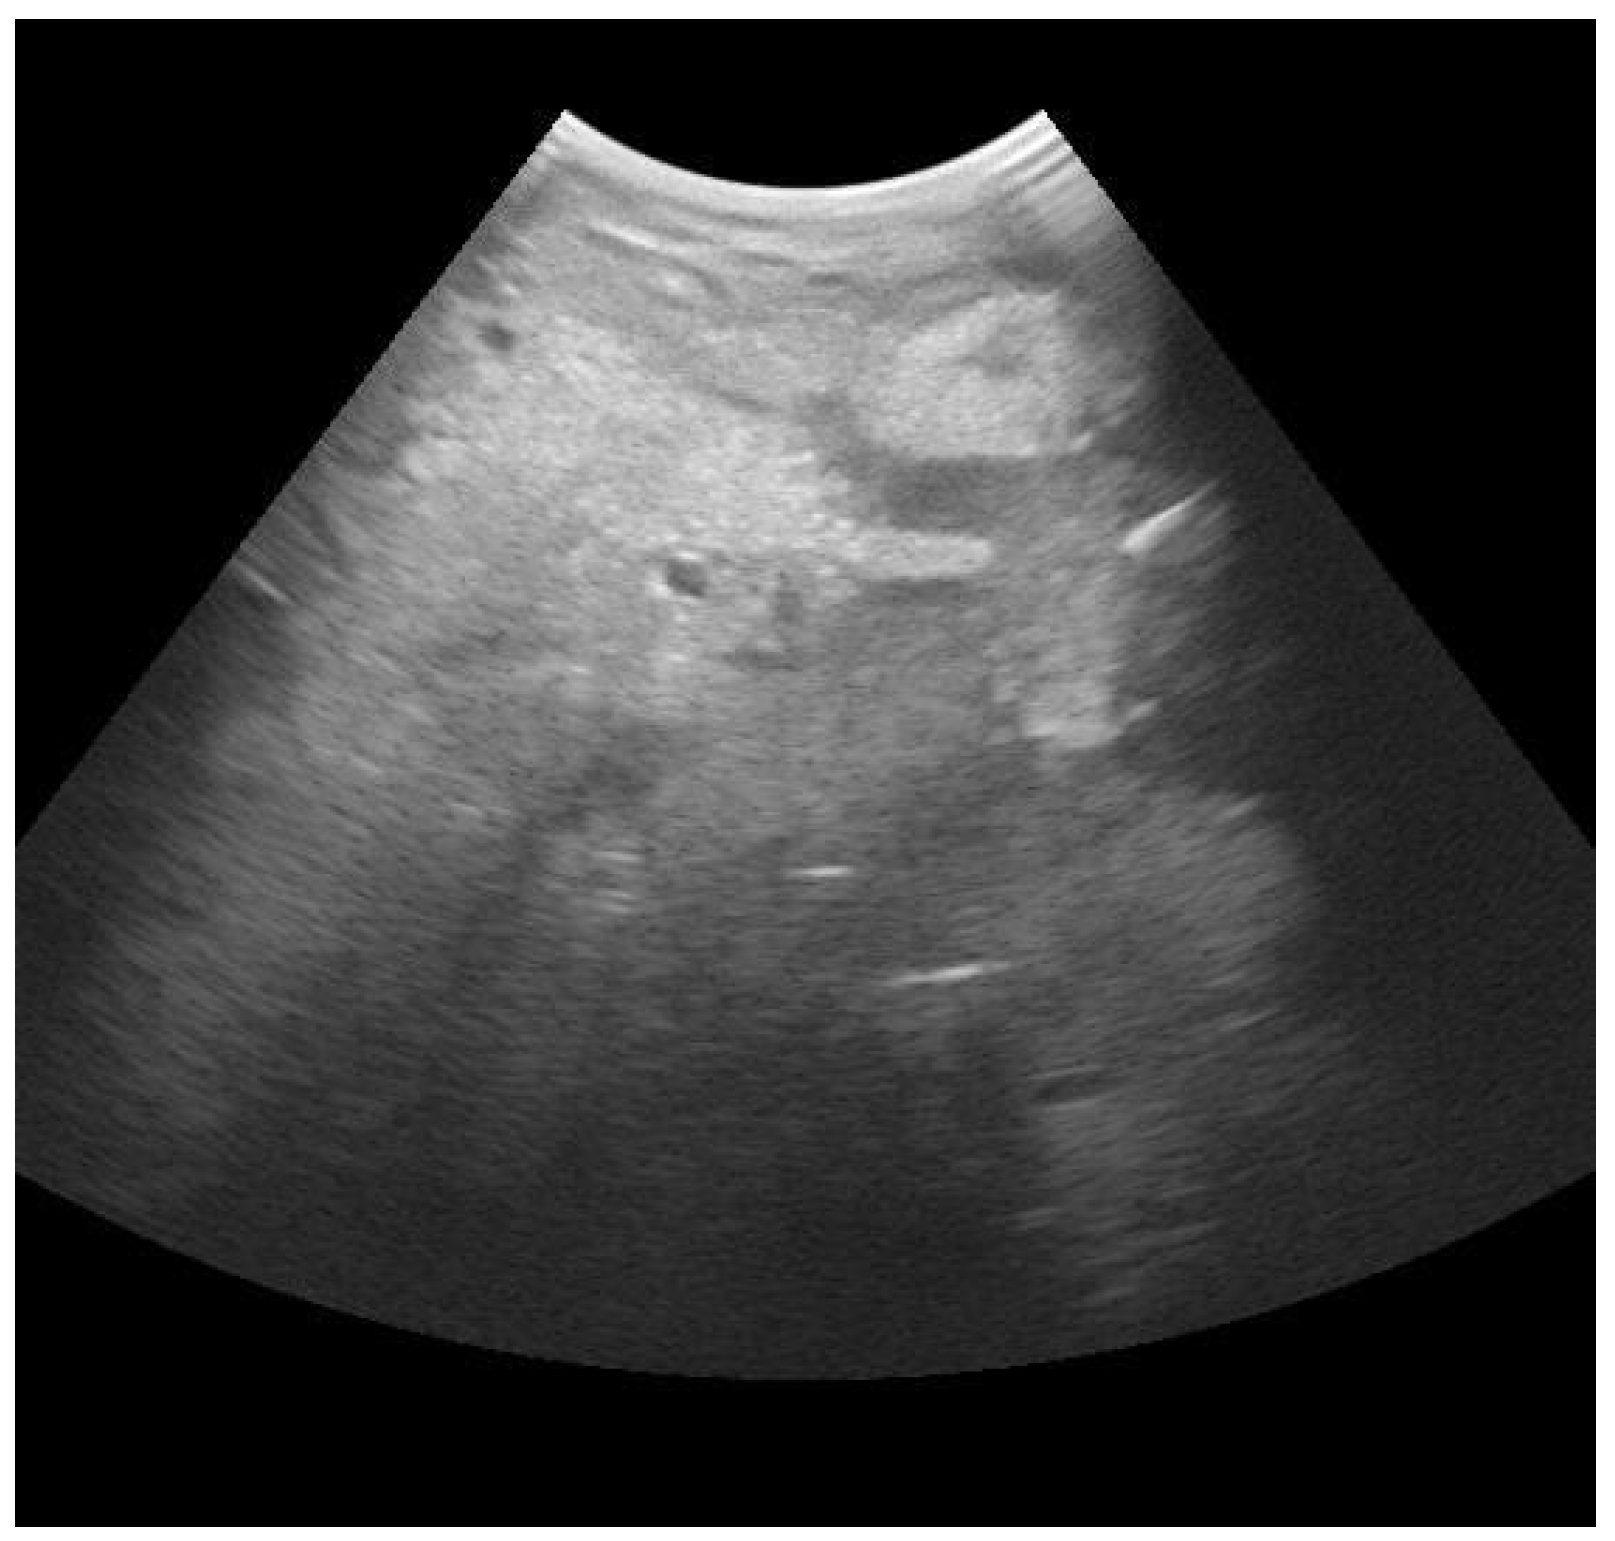

3.1. Mammary Ultrasound

- Fasulkov, I.R. Ultrasonography of the Mammary Gland in Ruminants: A Review. Bulg. J. Vet. Med. 2012, 15, 1–12. [Google Scholar]

- Suzuki, N.; Kurose, T.; Kaneko, S.; Haraguchi, A.; Isobe, N. Outcome Prediction from the First Examination in Clinical Mastitis Using Ultrasonography in Dairy Cows. Anim. Sci. J. 2020, 91, e13452. [Google Scholar] [CrossRef] [PubMed]

- Aishwarya Sunder, H.; Gupta, D.; Singh, R.; Singh, S.; Randhawa, C. Ultrasonographic Changes in Teat and Supramammary Lymph Nodes in Dairy Cows Affected with Clinical Mastitis. Haryana Vet. 2022, 61, 68–71. [Google Scholar]

- Flöck, M.; Winter, P. Diagnostic Ultrasonography in Cattle with Diseases of the Mammary Gland. Vet. J. 2006, 171, 314–321. [Google Scholar] [CrossRef]

- Mourya, A.; Shukla, P.C.; Gupta, D.K.; Sharma, R.K.; Nayak, A.; Tiwari, A.; Singh, B.; Singh, A.P.; Sahi, A.; Jain, A. Ultrasonographic Alteration in Subclinical Mastitis in Cows. J. Entomol. Zool. Stud. 2020, 8, 2058–2063. [Google Scholar]